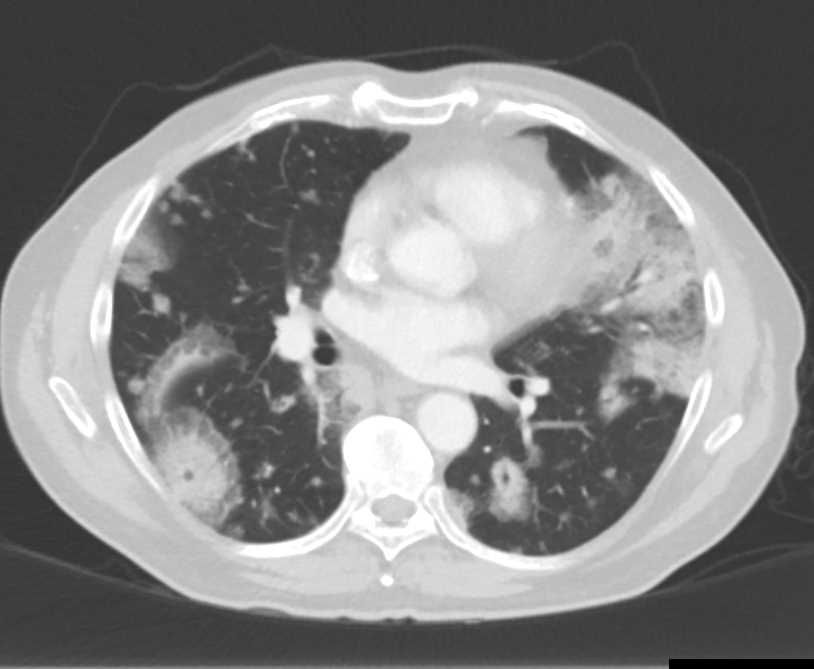

Dilated Aortic Root